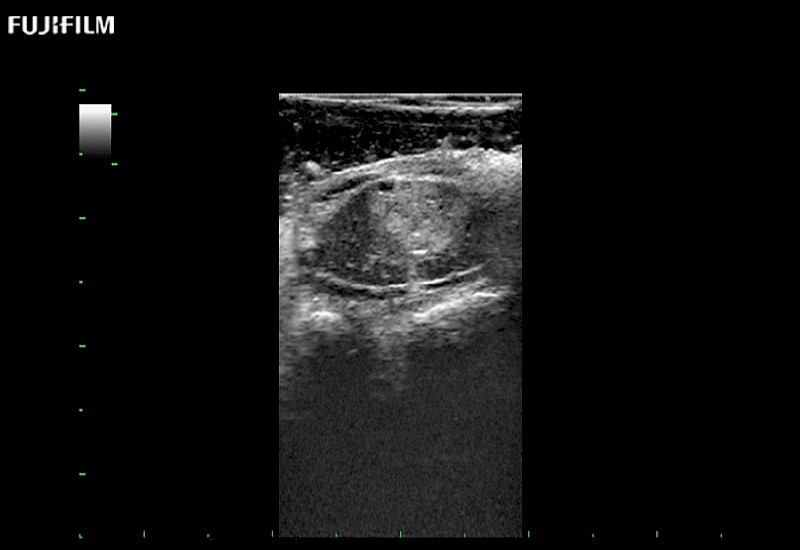

Extraordinary high-resolution digital imaging

Exceptional transducers

for use during: Cranial guidance, Burr-Hole guidance, Spinal Cord guidance, Pituitary guidance, Micro-Surgery guidance